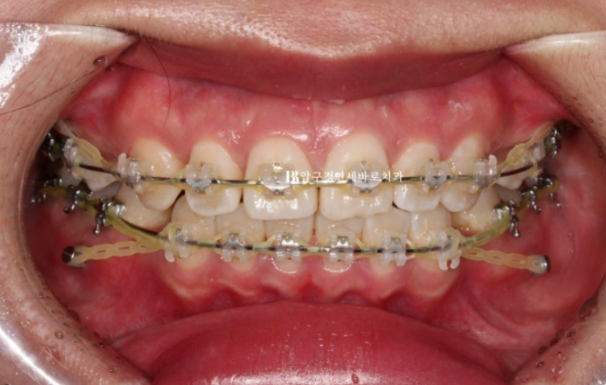

23.09

치료시작 7개월째 모습입니다.

이제 막 발치공간이 없어지면서 앞니가 뒤로 들어가기 시작하는 단계입니다.

24.03

치료시작 1년 1개월째 사진입니다.

발치공간은 모두 없어졌고 미니스크류를 이용하여 중심선을 맞추고 있습니다.

마무리 과정이라고 부르는 단계입니다.